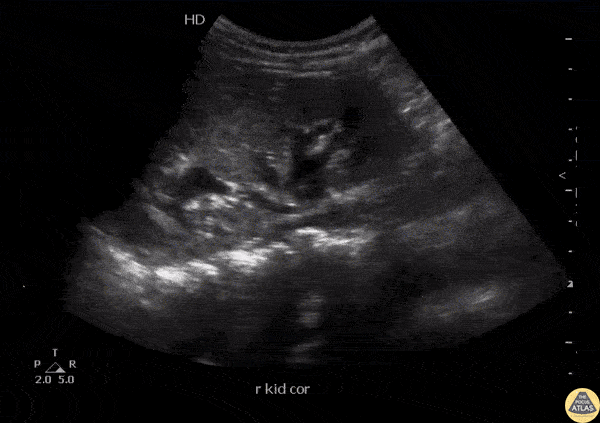

A young patient presented to the ED with abdominal and back pain. POCUS revealed a hyperechoic stone with acoustic shadowing within the right ureteropelvic junction. Image courtesy of Robert Jones DO, FACEP @RJonesSonoEM Director, Emergency Ultrasound; MetroHealth Medical Center; Professor, Case Western Reserve Medical School, Cleveland, OH View his original post here